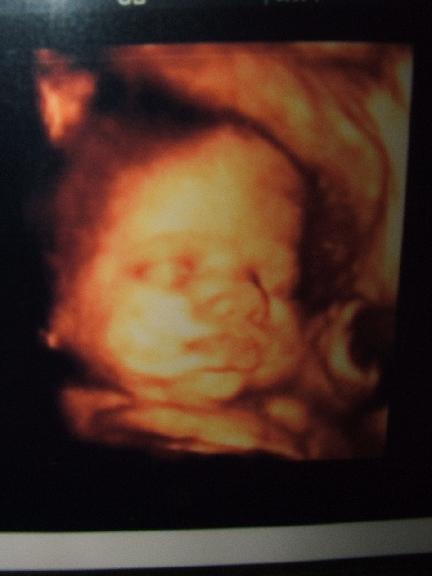

Ma voltunk Uh-n, megpróbálom feltenni nektek a képet, amit kaptunk. Olyan szép lett, teljesen látszik az arca. :) Már nagyon kíváncsi vagyok.

Bpd-je 92-es. :shock: Kis kerek buksis baba lesz. Súlya: 2300gramm.

Az első a két testvér. Zsófi a pocakban, és BOri. Sztem nagyon hasonlítanak.

Ez pedig a tegnapi uh kép:

Lili, milyen jok ezek az uh kepek! Nagyon jol latszik Boti arca! :D Tenyleg nagyon hasonlit Zsofira! :D

Lili: aztaa , hogy te milyen csuda szuper képet kaptál Botikáról! Mintha nem is a pocakban lenne. Szerintem is nagyon hasonlítanak egymásra Zsófikával. Az első 2 kép olyan mintha egy babáról készült volna... :shock: :wink: :lol: :lol: :lol:

Egyébként Erszényke, olyan érdekes, mert Boti szinte mindig mutatja az arcát uh-n. A nőgyógyász is ugye megnéz uh-val a havi kontrollokon, és ott is mindig mutatja a doki, h. nézze, ott van az arca. Telibe mindig. ÉS nem gondoltam volna, h. most itt is sikerül elkapni. Még csücsörített is. :)